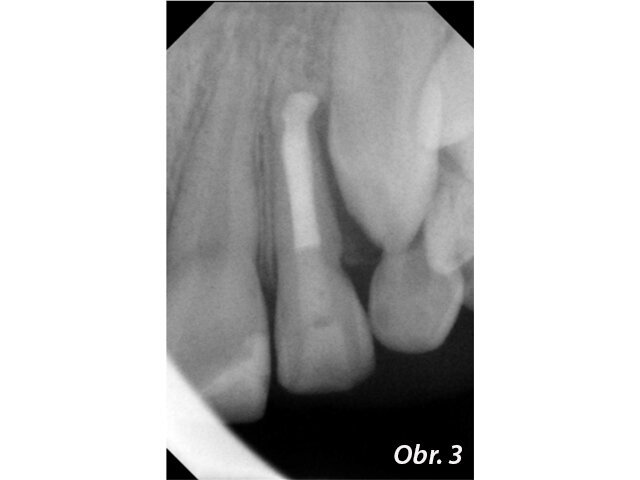

Stav před endodontickým ošetřením (Fotografie: MUDr. Hana Zallmannová)

Zánětlivé změny v periapikálních tkáních a současně schopnost hypochloridu rozpouštět měkké tkáně mohou vést ke vzniku prázdného prostoru periapikálně. Pravděpodobnost přetlačení MTA do periapikálního prostoru je pak velká. Vzhledem k biokompatibilitě tohoto materiálu se nejedná o komplikaci, která by ohrožovala výsledek ošetření (obr. 1–4), není však žádoucí. Pokud periapikální tkáně nevytvářejí přirozenou bariéru, která přetlačení MTA brání, je možné takovouto bariéru vytvořit z kolagenu.